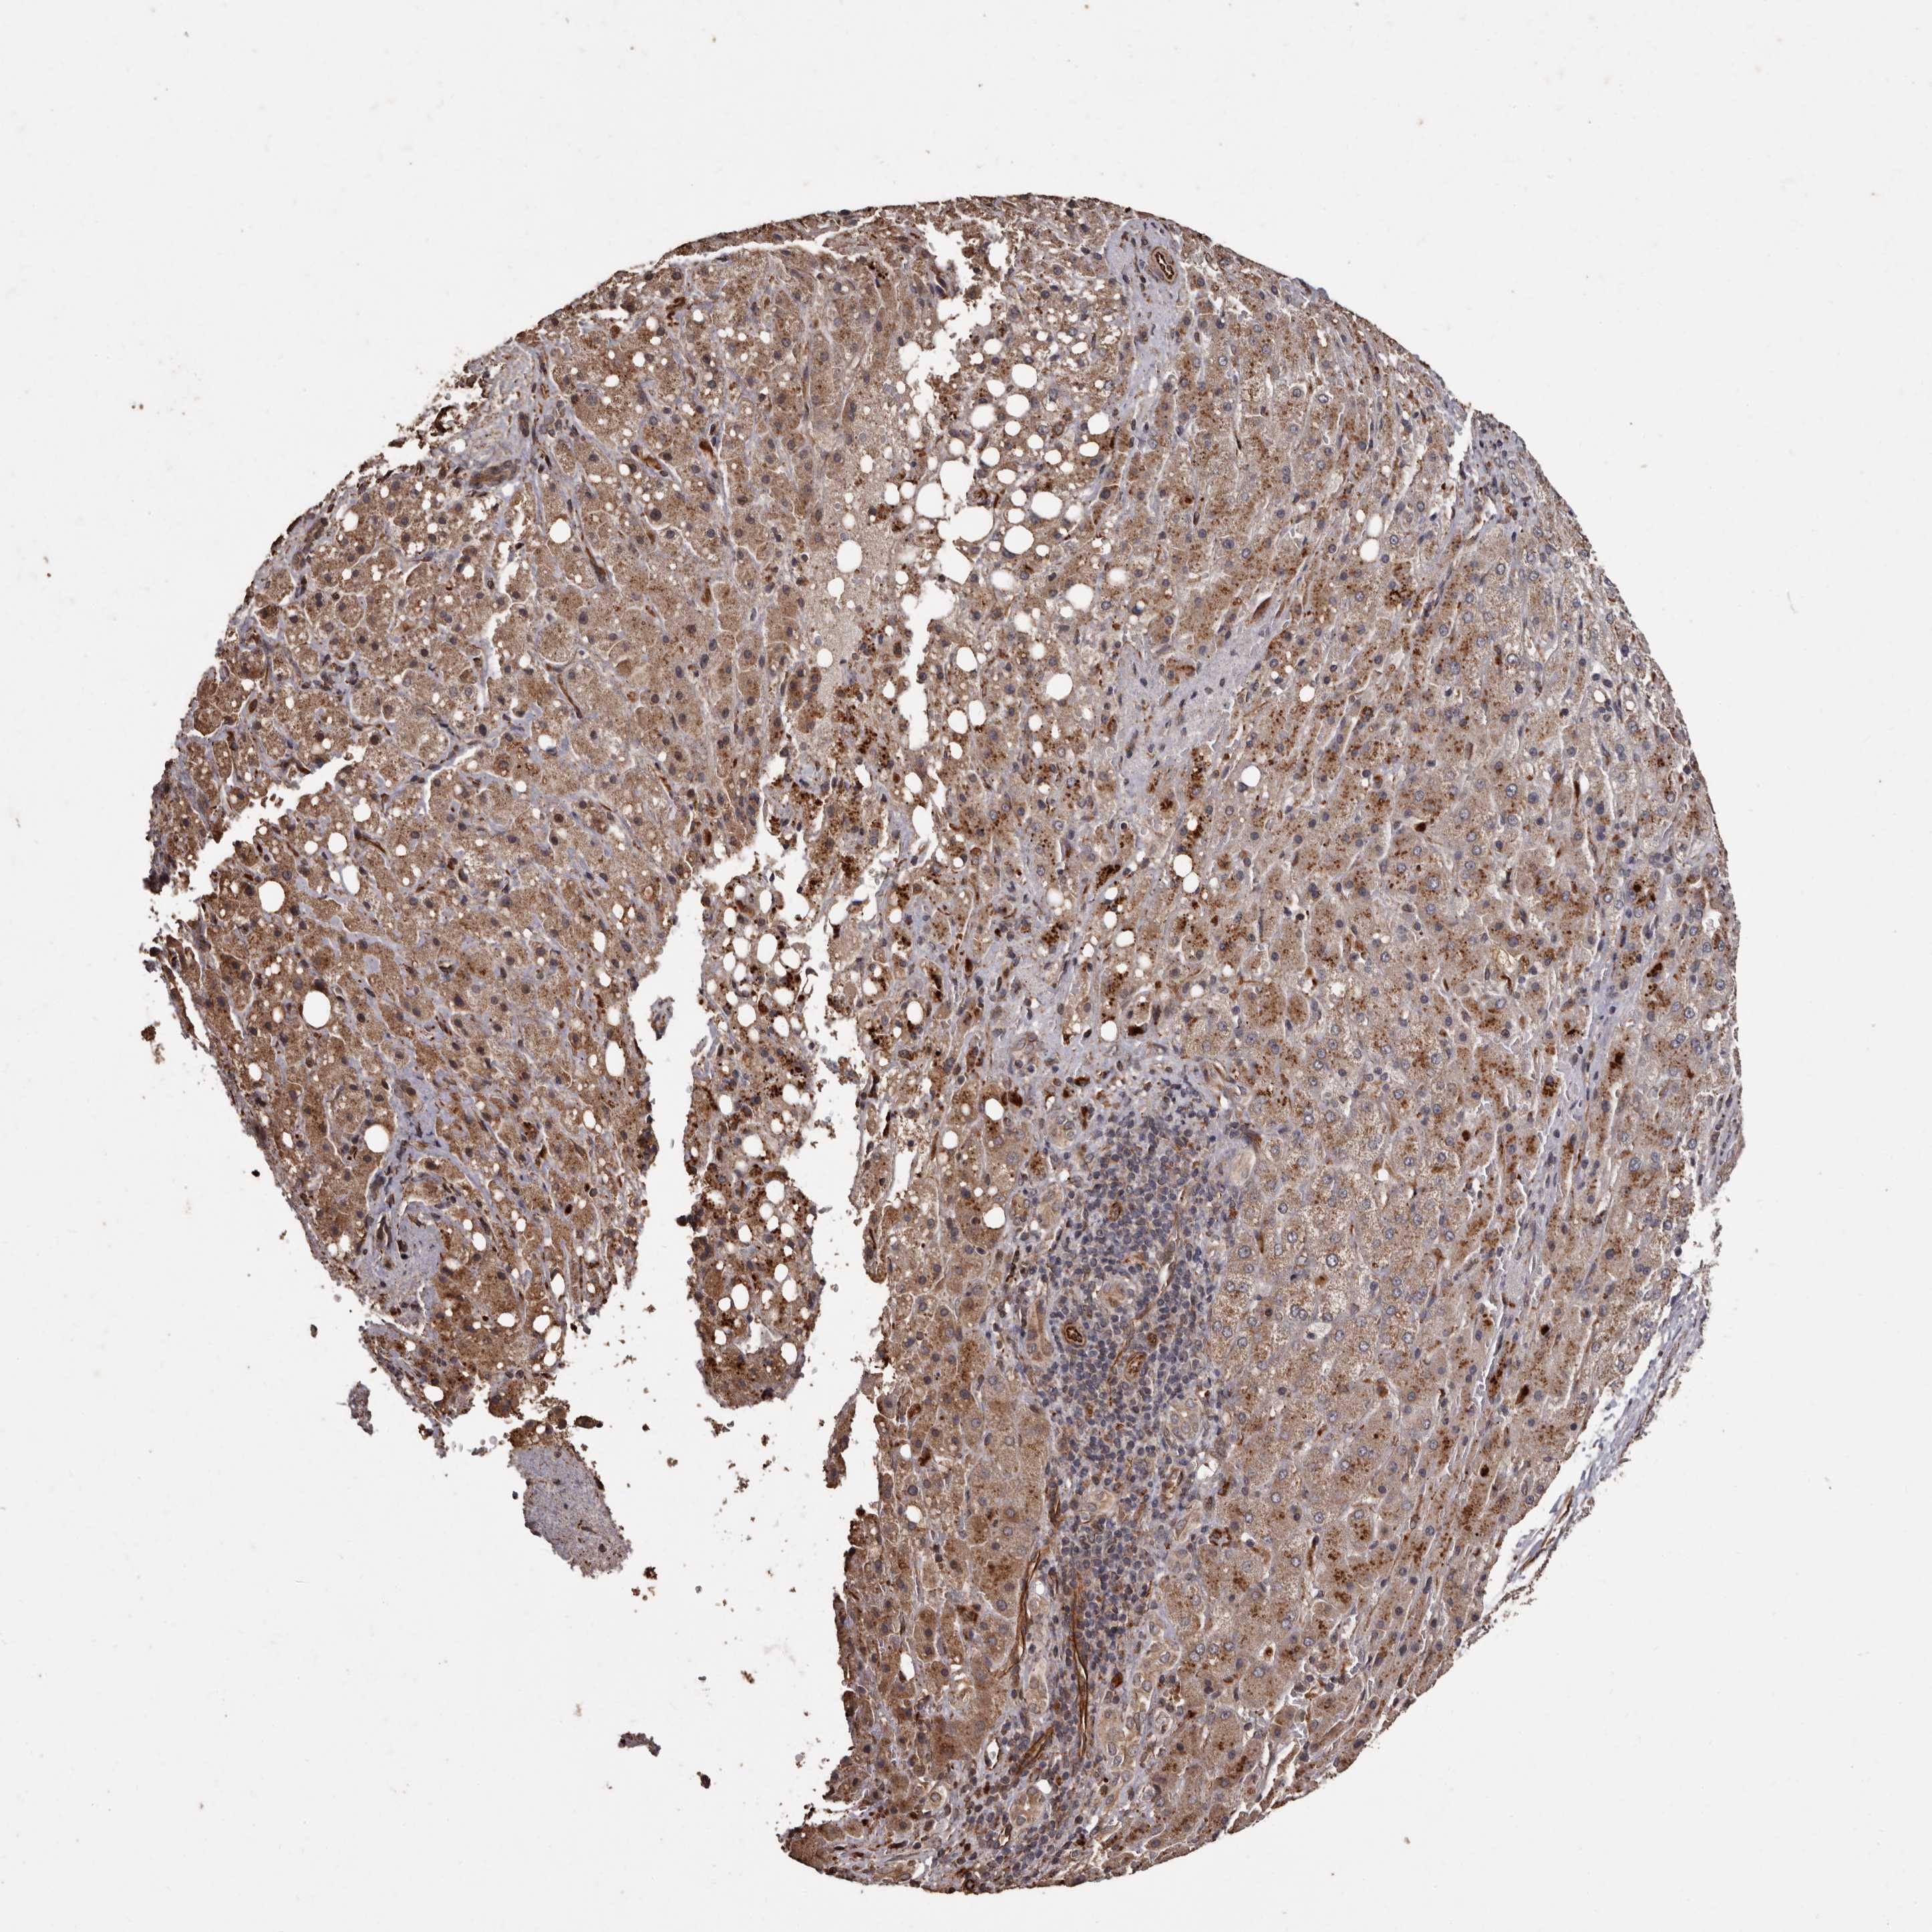

LIVER CANCER - Protein expressioni

A mouse-over function shows sample information and annotation data. Click on an image to view it in a full screen mode. Samples can be filtered based on level of antibody staining by selecting one or several of the following categories: high, medium, low and not detected. The assay and annotation is described here.

Note that samples used for immunohistochemistry by the Human Protein Atlas do not correspond to samples in the TCGA dataset.

Antibody stainingi

Antibody staining in the annotated cell types in the current human tissue is reported as not detected, low, medium, or high, based on conventional immunohistochemistry profiling in selected tissues. This score is based on the combination of the staining intensity and fraction of stained cells.

Each image is clickable and will lead to virtual microscopy that enables deeper exploration of all samples and also displays staining intensity scores, fraction scores and subcellular localization as well as patient and tissue information for each sample.

Antibody HPA029455

Staining

High

Medium

Low

Not detected

Intensity

Strong

Moderate

Weak

Negative

Quantity

>75%

75%-25%

<25%

None

Location

Nuclear

Cytoplasmic/membranous

Cytoplasmic/membranous,nuclear

Cholangiocarcinoma

Carcinoma, Hepatocellular, NOS